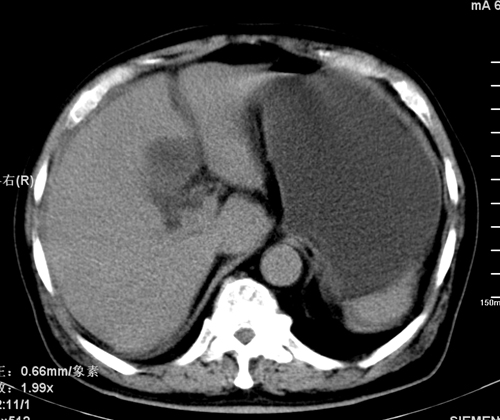

以下是引用liaoqiang在2008-3-27 15:57:00的发言:[br]1右肾脏周多发大小不一球形影,考虑肾脏囊肿可能性大。2胆囊边界欠清楚。考虑胆囊炎可能性。

以下是引用随光逐影在2008-3-27 16:33:00的发言:[br]考虑为:1)双肾囊肿可能。2)急性胆囊炎。建议:行进一步检查。